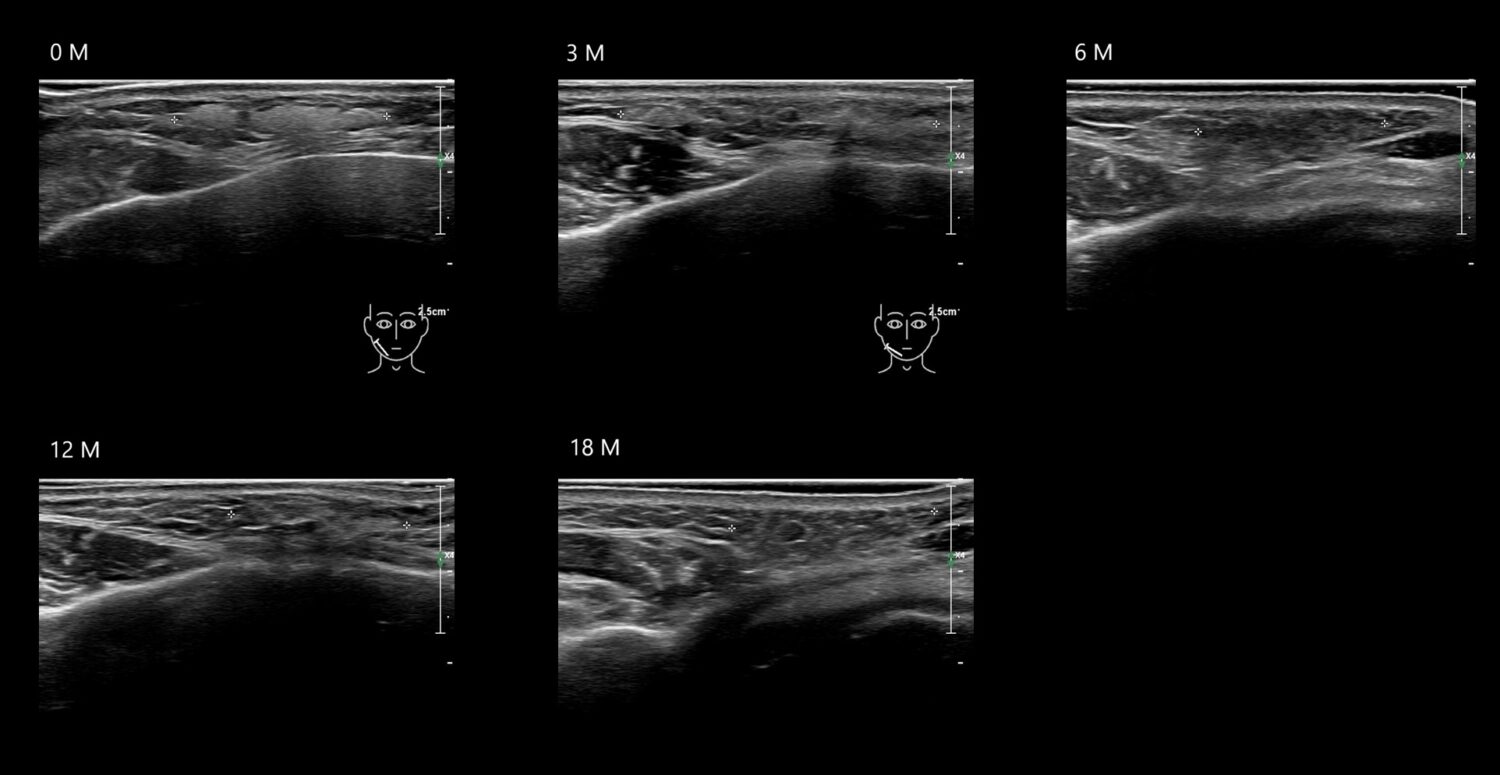

HAca13e